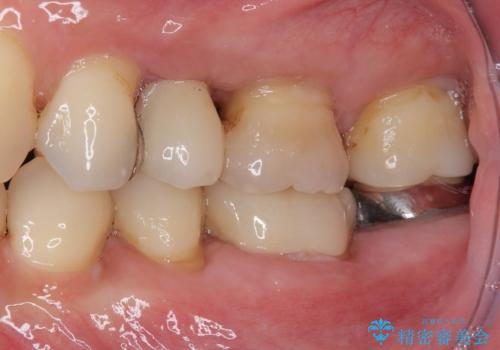

埋入から2ヶ月ほどでインプラントの十分な生着が認められ、処置した歯肉も綺麗に治癒したため、速やかに補綴治療を行いました。

補綴治療後3ヶ月での経過は良好で、引き続き経過観察を行っていきます。